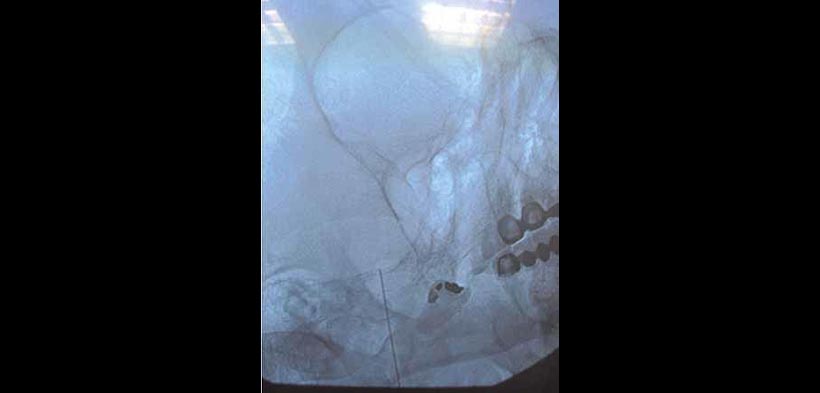

Fig. 1. Rizotomía percutánea con radiofrecuencia. Colocación del paciente en decúbito ventral con hiperextensión.

Fig. 2. Rizotomía percutánea con radiofrecuencia. Visualización del agujero oval con la utilización de un equipo de rayos en proyección anteroposterior o ligeramente caudocraneal.

Fig. 3. Rizotomía percutánea con radiofrecuencia. Se marca el punto de entrada sobre la piel que generalmente se encuentra a dos traveses de dedo de la comisura bucal. Se inyecta anestesia local y posteriormente se accede al ganglio con una aguja desechable de radiofrecuencia.

Fig. 4. Rizotomía percutánea con radiofrecuencia. La técnica clásica consiste en localizar la rama a lesionar mediante estimulación sensitiva a 50 H entre 0-1 voltio y generar posteriormente lesiones sucesivas a partir de 60° centígrados en adelante durante 60 segundos cada lesión hasta conseguir hipoestesia en la zona deseada de la cara.